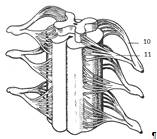

Спинной мозг. Внешнее строение. Сегменты

Спинной мозг (medulla spinalis) лежит в

позвоночном канале и представляет собой полный цилиндрический тяж, уплощенный в

дорсовентральном направлении и имеющий два утолщения: шейное (intumescentia

cervicalis – 3), и поясничное (intumescentia lumbalis – 5). Снаружи спинной

мозг покрыт тремя оболочками: мягкой, или сосудистой, паутинной и твердой.

Спинной мозг делится на две симметричные

половины передней срединной щелью (fissura mеdiana

anterior) и задней

срединной

бороздой

(sulсus

medianus posterior). От каждой из этих половин из боковых

бороздок отходят два продольных ряда корешков (radix) спинномозговых нервов

(1). Передние корешки (11) образованы эфферентными отростками нейронов спинного

мозга, задние (10) – афферентными отростками нейронов спинномозговых узлов.

Соединяясь друг с другом передние и задние корешки образуют спинномозговые

нервы (нижний рисунок). Ниже второго поясничного позвонка пучок корешков,

образует так называемый конский хвост (cauda equína – 9).

Участок

спинного мозга, соответствующий двум парам корешков спинномозговых нервов,

называют сегментом спинного мозга. В спинном мозге насчитывается 31 сегмент: в

шейном отделе – 8 сегментов; в грудном – 12; в поясничном и крестцовом – по 5;

в копчиковом – 1. Спинной мозг покрыт тремя оболочками – сосудистой, паутинной

и твёрдой.